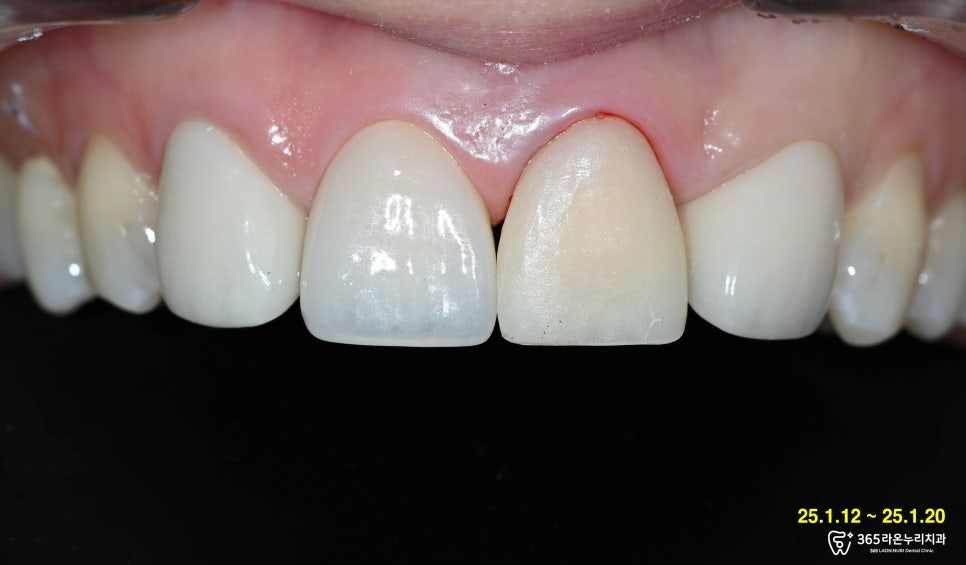

정면에서 왼쪽 앞니가

깨져 나간 것을 확인할 수 있었습니다.

최종 크라운을 끼운 후의 모습입니다.

지르코니아 크라운의 경우

모양을 정교하게 만들고

제작 진행 과정은 골드

크라운보다 까다롭기에,

정밀하게 제작하는데 몰두했습니다.

그렇게 최종 크라운 형태 및

쉐이드 모두 기존 이와

유사하게 나와 심미보철

또한 높은 진료 퀄리티로

만족시켜드릴 수 있었습니다!

어디를 진료했는지 모를 정도로

기존 영구치와 정말 유사한 색을 띕니다.

교합 관계까지 고려하여 제작해드린 덕분에,

앞니끼리의 맞물림이 편안하고

보기에도 심미적이지요?

잇몸 모양이 예쁘게 잡히면서

보철의 경계도 드러나지 않습니다.